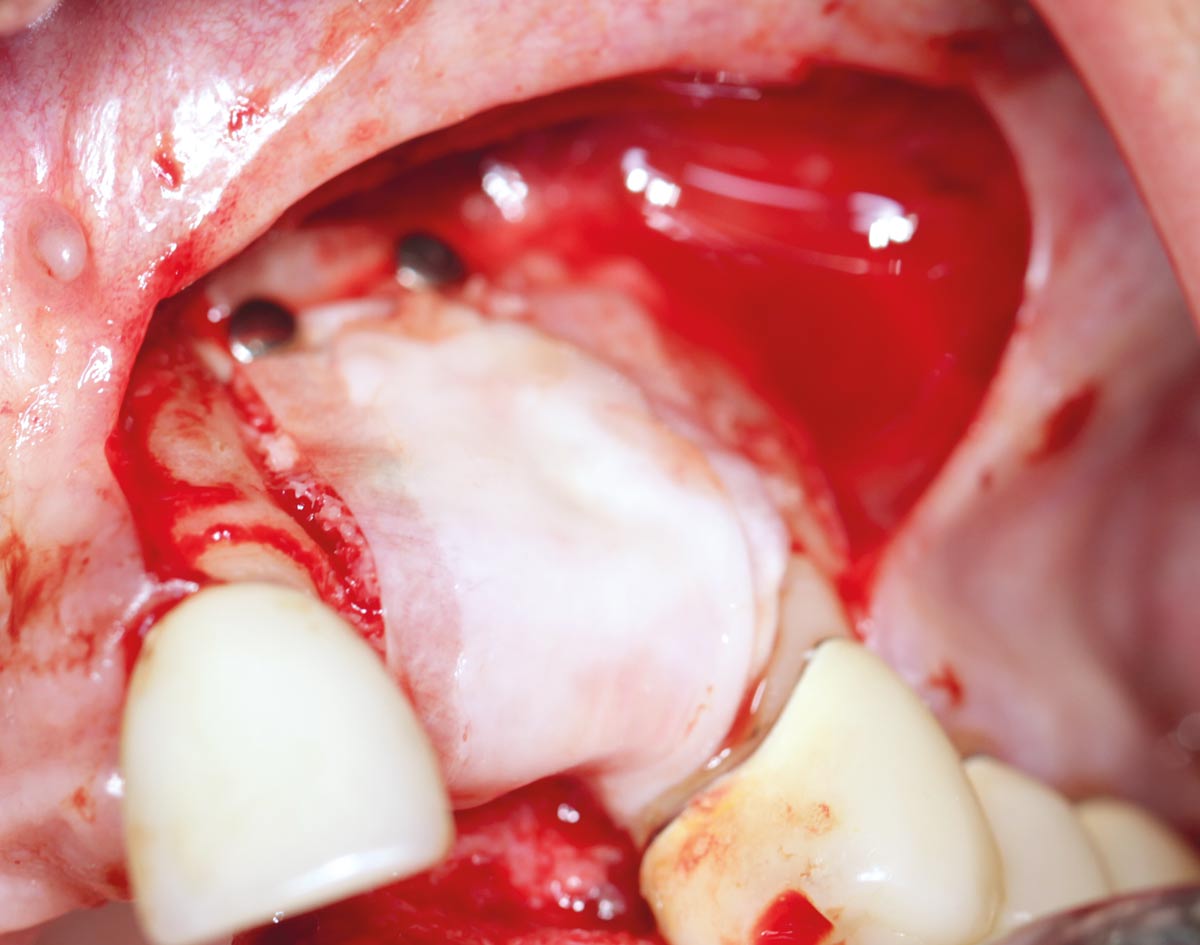

Restoration of all four incisors with two maxgraft® bonering - Dr. B Giesenhagen

Initial situation pre-op: Central incisors with mobility 3